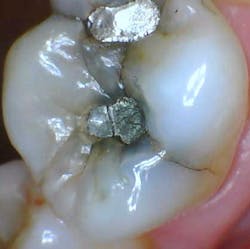

- 62-year-old female, new-patient exam/full assessment

- Asymptomatic tooth no. 14

- Arguably conservative lingual/mesial/distal pit occlusal amalgams with a small fracture on the mesial restoration

- Noted fracture lines across the transverse and mesial marginal ridges as well as lingual and buccal grooves

- Amalgam salt leakage/staining of the tooth with likely caries that’s not clinically or radiographically evident, especially where the amalgam is cracked